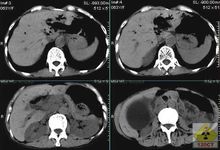

CT檢查

硬化性膽管炎CT(computerizedtomography)CT能較好地顯示含鈣結石及肝門區的解剖關係,可提示此綜合徵與其他疾病鑑別診斷的徵象。CT主要表現為:膽囊頸增寬;膽囊外的含鈣結石;靠近膽囊有一個不規則的囊腔;胰腺段以上膽管梗阻徵象。肝門區多囊多管征和肝門區擴張的膽管壁增厚以及肝門區各結構之間的脂肪間隙顯示模糊和消失徵象,後者是由於膽囊頸或膽囊管嵌頓結石引起膽囊管擴張、扭曲和膽囊周圍炎的表現。如CT未顯示含鈣結石,但有胰上段的膽管擴張、增厚、肝門區脂肪間隙顯示不清及消失,也應考慮此綜合徵的可能。但應與腫瘤及其他疾病引起的類似徵象鑑別。由於CT橫斷面的限制,常不能顯示膽囊頸/管結石嵌頓壓迫肝總管的直接徵象,與超聲相比並無更多優勢,但隨著螺鏇CT三維重建技術的開發及在膽

系疾病中的套用,在此綜合徵的診斷中具有一定的潛力。